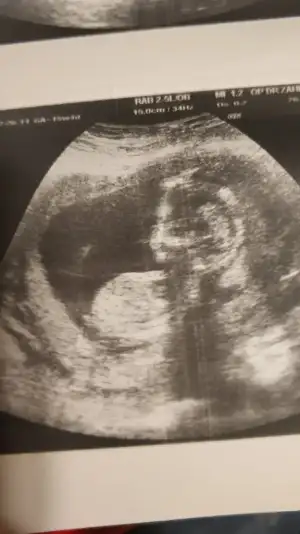

Kız gibi gibi diyorum net değil usg başka varsa paylaşın emin olamadım12+4 günlük yorumlayabilir misiniz![]()

Sanki kız gibi ama emin değilim nubu karanlık kalmış 12 yada 13 haftada paylaşın emin olmak istiyorum![]()

Kız gibiIkra meyra tekrar usg paylaşın demiştiniz sat a göre 12+1 ultrasona göre 12+6 çıktık ❤Pazartesi tekrar gideceğim ama bunu da atmak istedim belki bir tahmin olur

![]()